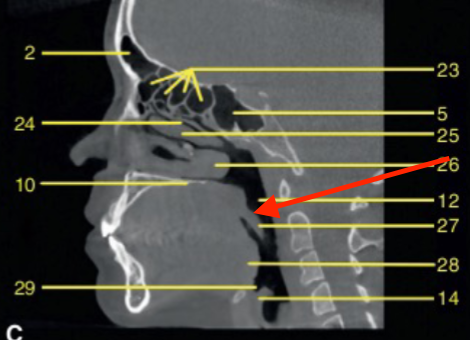

identify 5

soft palate

sella turcica

identify the structure

C1